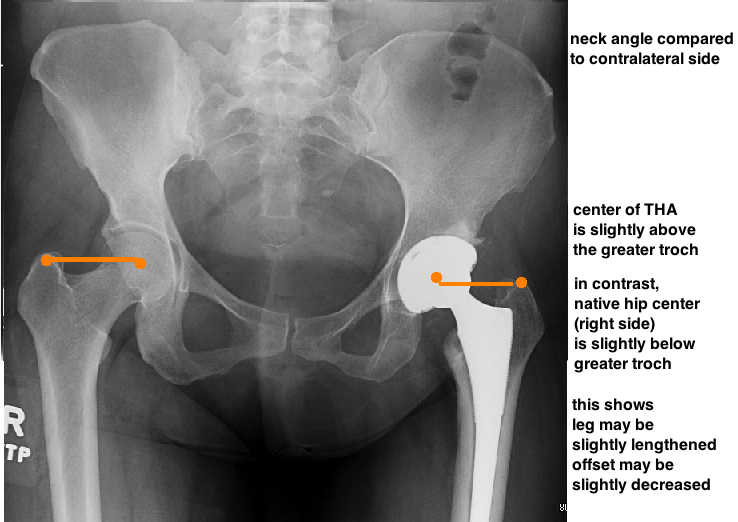

THEN EVALUATE STEM PLACEMENT.